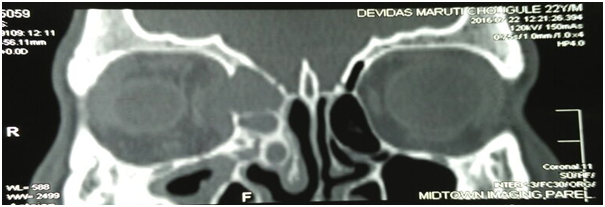

A 22years old male presented with bilateral blocked nose sensation (right>left) since 7-8months, persistent frontal headache. History of right sided facial heaviness and pain with right periorbital swelling. No history of trauma, clear fluid discharge from nose. No history of recurrent episodes of upper respiratory tract infections/ recurrent episodes of sneezing/running nose or any previous trauma. On examination, anterior rhinoscopy showed mucopurulent discharge and crusting, nasal endoscopy showed bilateral inferior turbinate hypertrophy, mucosa was normal. CT scans of paranasal sinuses showed large homogenous expansile cystic lesion obstructing the right frontal sinus drainage. Another homogenous mass was noted in extending to the right ethmoid sinus suggesting the possible diagnosis of two separate frontal and ethmoid mucoceles with pansinusitis and right sided proptosis (Figure 1-3).

Figure 1 & 2 CT scans showing homogenous masses in the right frontal and ethmoid sinuses.

Figure 3 CT scan suggestive of right side proptosis.